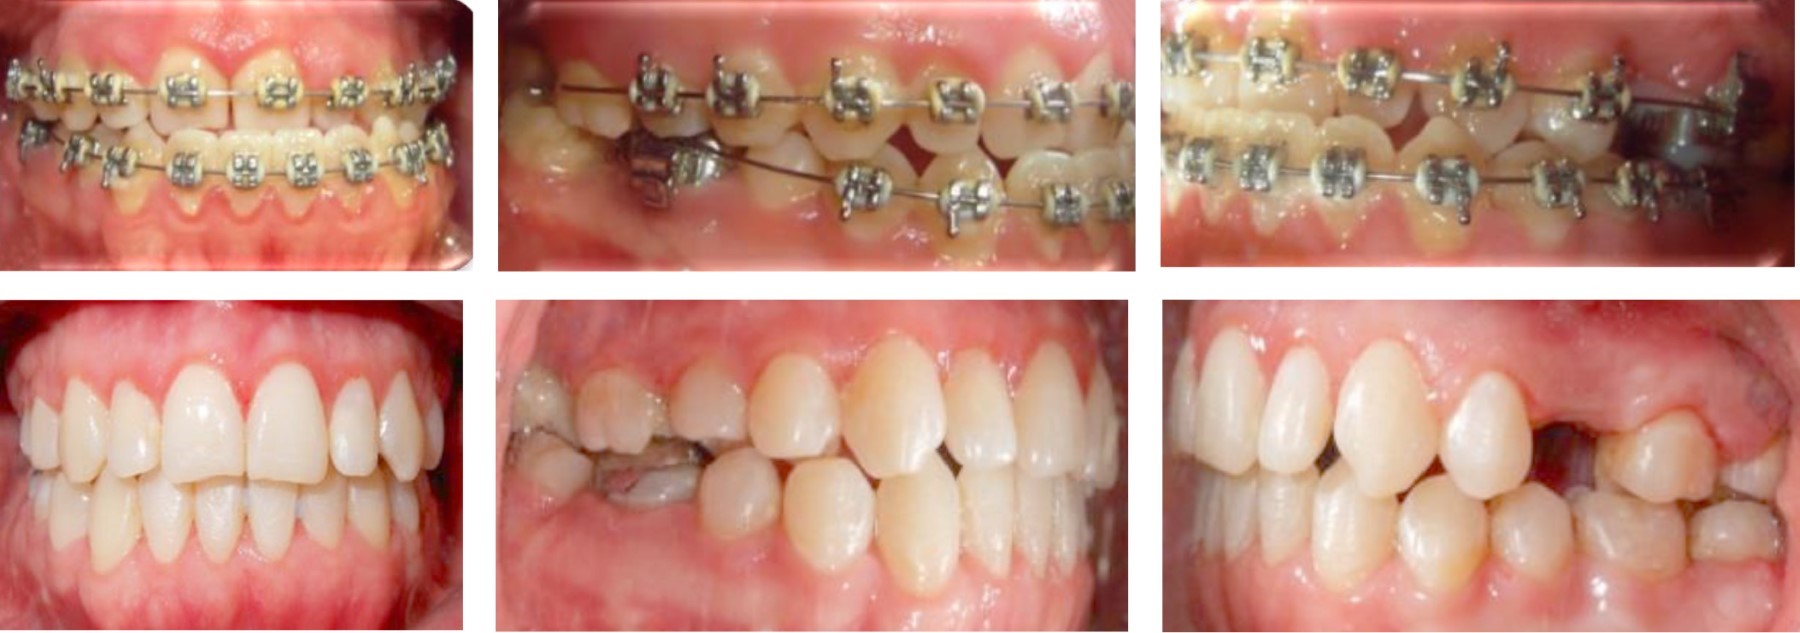

RESULTS

The treatment was completed in 23 months, in which the profile was improved, the gingival smile was eliminated, providing facial harmony (Figure 12). The crossbite was eliminated leaving a more stable case, providing an adequate dental harmony, class I canine, and bilateral molar. It was possible to center the dental midlines, improve the shape of the arches, and vertical and horizontal overbite (Figure 13). The dental inclinations were improved and skeletal class I was achieved (Figure 14). A circumferential retainer was placed to improve the occlusal set. After two months, the occlusal adjustment was performed (Figure 15). The changes obtained can be observed facially (Figure 16), occlusally (Figure 17), and radiographically (Figures 18 and 19).

Figure 12

Figure 13

Figure 14

Figure 15

Figure 16

Figure 17

Figure 18

Figure 19